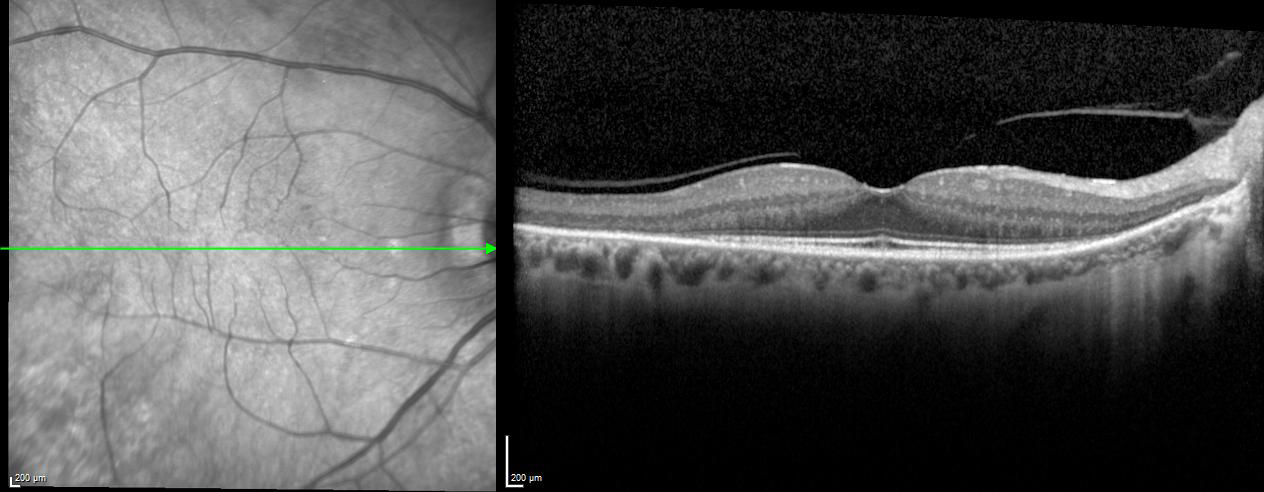

EDI – Enhanced Depth Imaging Mode

The Enhanced Depth Imaging Mode (EDI) of the SPECTRALIS is an OCT imaging technology that enables better visualization of choroidal vasculature. By automatically inverting the image and leveraging the benefits of technologies like TruTrack Active Eye Tracking and Noise Reduction, SPECTRALIS delivers superior images to depict the choroid, allowing to manually measure choroidal thickness.

Retinal and choroidal thickness in pediatric patients with sickle cell disease: a cross-sectional cohort study

An Evaluation of Choroidal and Retinal Nerve Fiber Layer Thicknesses Using SD-OCT in Children with Childhood IgA Vasculitis